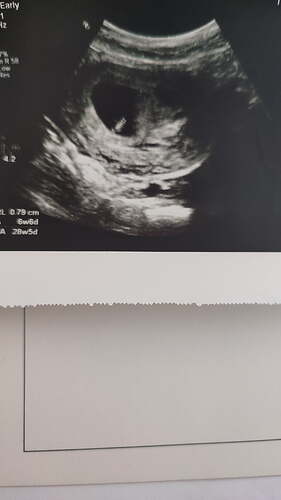

Bu usg 6 haftalik henuz sanirim yeni ultrason fotosu varmi

Nub olayından hiç anlamıyorum ki :joy:

Bende cizdim erkek gibi geldi ustte cikinti nub olabilir die ama baska biryerde net kiz bu diyenler olmus doktorda kiza benzetti gbi

Nub öğrensek köşeyi döneriz :joy: